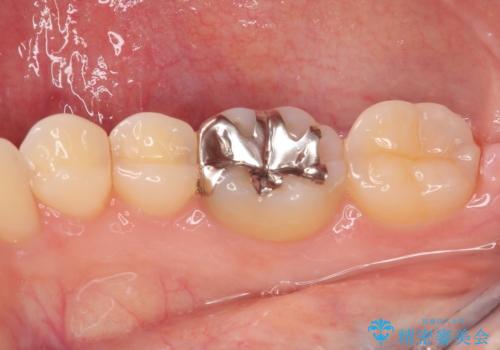

金属の詰め物が目立つのでやり替えたい ハイブリッドインレー修復

- 銀歯をやり替えたいとのことで来院された患者様です。金属の詰め物の大きさ、虫歯の範囲を考慮してオールセラミッククラウンでの治療をご提案しましたが、患者様のご希望であまり歯を削りたくないとのことでハイブリッドインレーでの治療を行うことにしました。